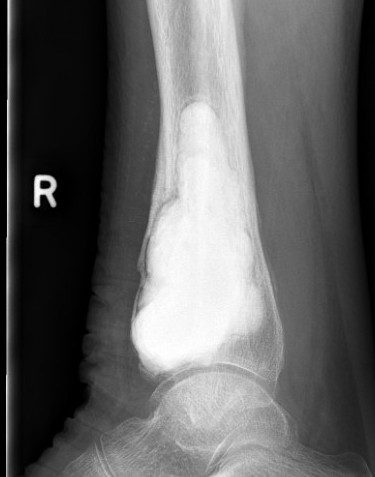

X-ray

Eccentric, sharply demarcated lytic lesion

- no sclerosis around lesion

- narrow zone of transition

- metaphysis, extending into epiphysis

- no mineralization

Distal Radius

Abuhejleh et al Eur J Orthop Traumatol Surg 2020

- 57 patients with GCT's of distal radius

- 29% (10/34) recurrence with intra-lesional treatement but no complications

- 4% (1/23) recurrence with wide resection / arthrodesis but 30% complication rate

- increased risk recurrence for Grade 3

- wide resection / arthrodesis should be reserved for grade 3

Koucheki et al Eur J Orthop Traumatol Surg 2023

- systematic review of 13 studies and 373 patients

- increased local recurrence with intralesional versus en-bloc resection

- especially Grade 3

- increased complications and poorer function with en-bloc resection

Distal radius GCT treated with en bloc resection and allograft reconstruction, followed by late wrist subluxation